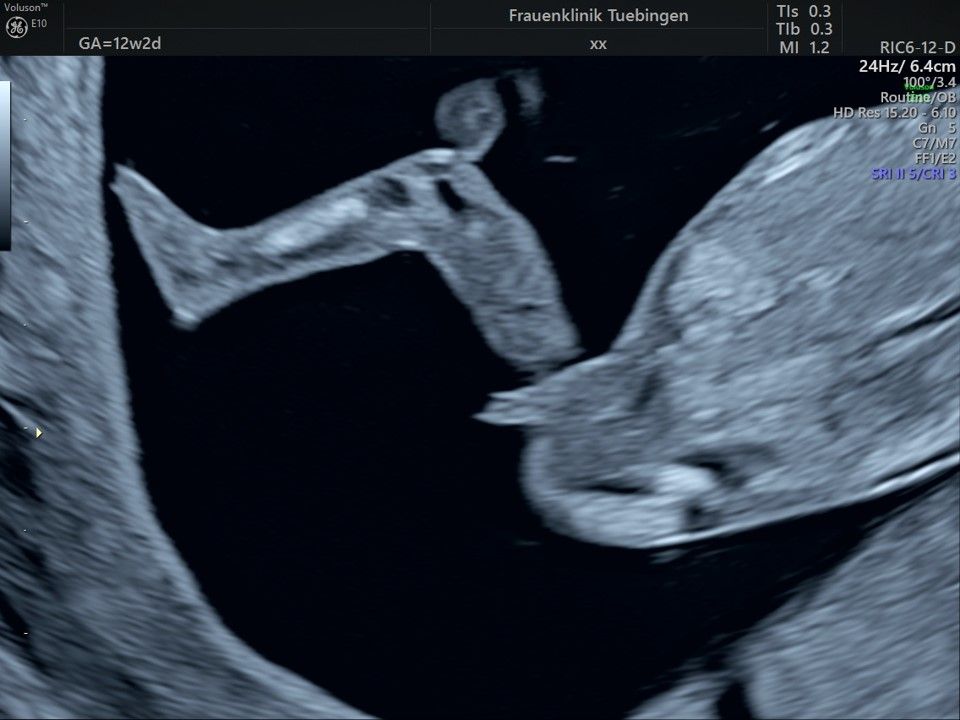

Im Rahmen des Ersttrimester-Screenings untersuchen wir die Organe des Feten mittels Ultraschall. Dabei machen wir auch gerne ein Bild für Sie.

Obwohl der Fet zu diesem Zeitpunkt erst zwischen 5 und 8cm groß ist, lassen sich bereits etwa die Hälfte aller schwerwiegenden Fehlbildungen erkennen bzw. ausschließen. Sollten wir eine Auffälligkeit sehen, werden wir mit Ihnen den Befund und das weitere Vorgehen ausführlich besprechen.

Fetale Anatomie